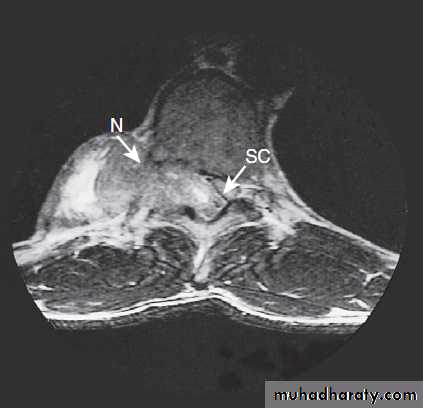

Different techniques of imaging the cervical spine. A Lateral X-ray showing bilateral C6/7 facet dislocation. B Myelogram showing

widening of cervical cord due to astrocytoma (arrows). C MRI showing posterior epidural compression from adenocarcinomatous metastasis to the posterior arch of T1 (arrows).